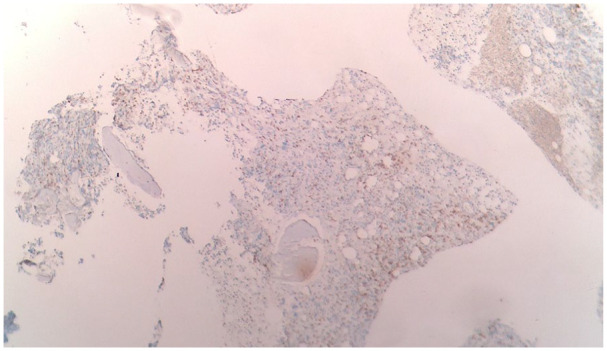

Abstract Image